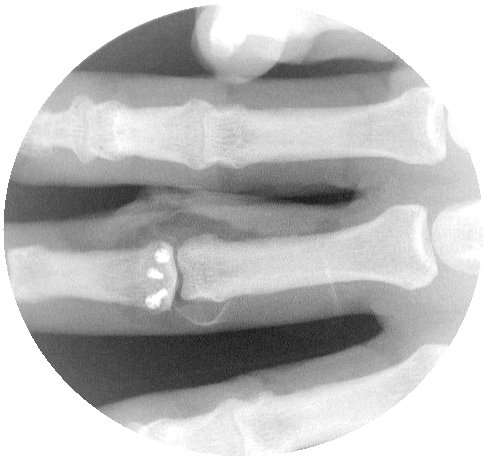

The dorsal hamate carpometacarpal area is used as a donor site for joint surface reconstruction. It has a "gull wing" biconcave contour which usually matches that of the missing finger joint surface.

Here, the graft has been harvested and sculpted to fit the remaining joint. Three 0.035" K wires are in place for provisional fixation.